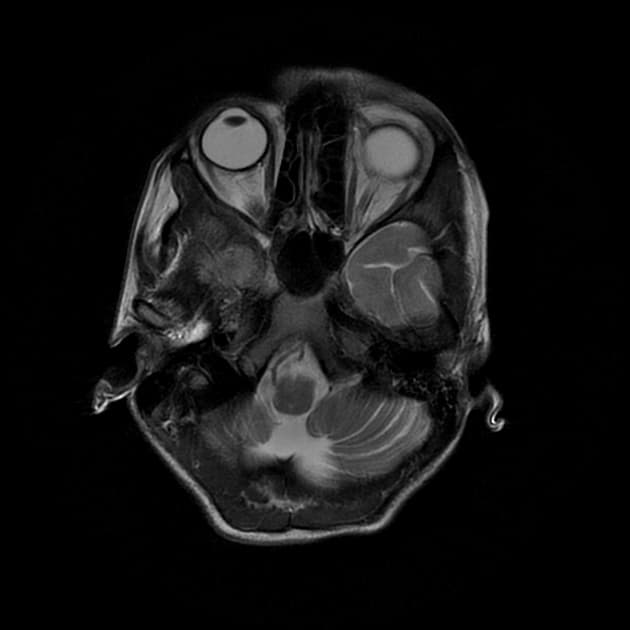

Chụp cộng hưởng từ (MRI) cho thấy các đặc điểm điển hình của bệnh xơ cứng rải rác. Ngoài ra, một số tổn thương có tín hiệu tăng trên hình ảnh T1 (T1 hyperintense).

- Các tổn thương rải rác, dạng vệt hoặc hình tròn, tăng tín hiệu trên hình ảnh khuếch tán (diffusion-weighted imaging), khu trú chủ yếu ở vùng chất trắng quanh thất (periventricular white matter), chất trắng ở bán nguyệt (juxtacortical white matter), thân gai thị – giao thoa thị giác (optic radiation – optic chiasm), và thân não (brainstem) – phù hợp với đặc điểm của xơ cứng rải rác (multiple sclerosis).

- Các cấu trúc não sâu như các nhân nền (basal ganglia) và thùy đảo (insula) không bị tổn thương.

- Đa giác Willis (Circle of Willis) và các động mạch não trước (anterior cerebral artery), động mạch não giữa (middle cerebral artery), động mạch não sau (posterior cerebral artery) thông thoáng, không thấy tắc mạch (occlusion), bóc tách (dissection) hay tuần hoàn bàng hệ (collateral circulation) bất thường.

- Không thấy xuất huyết (hemorrhagic), tăng tỷ trọng (hyperdense) hay huyết khối thành mạch (mural thrombus).